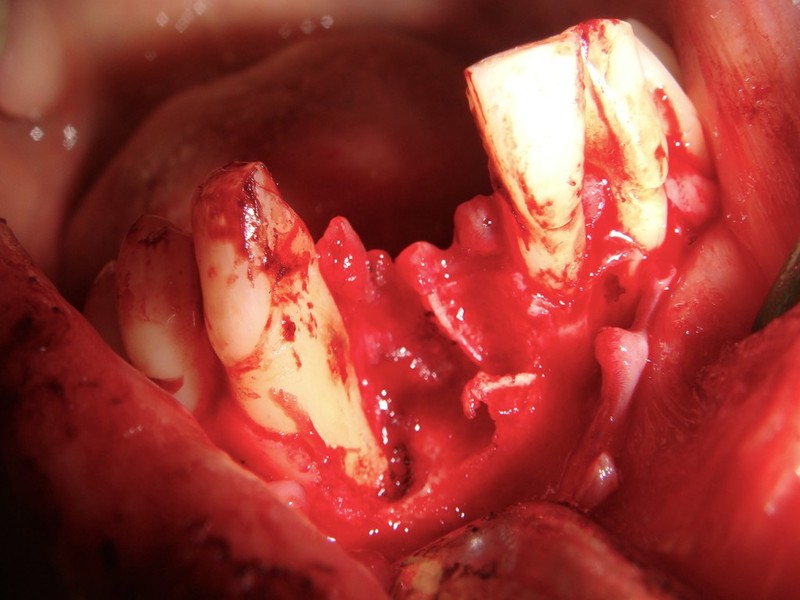

Estrazione di un canino incluso e contestuale inserimenti di impianto e innesto osso eterologo